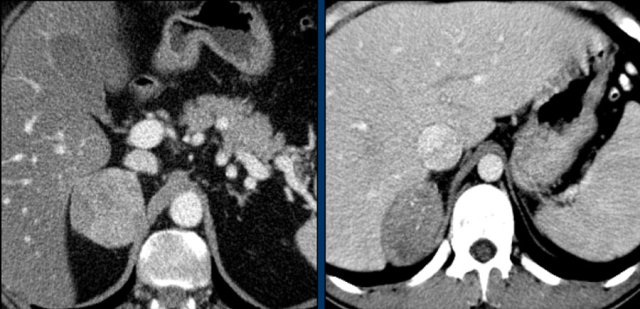

The images show bilateral adrenal incidentalomas found in a 64-year old patient scanned for analysis of an abdominal aneurysm.

The scan in the arterial phase shows bilateral lesions with a density of 50 HU.

On the non-enhanced CT performed a few days later, the density in both adrenal glands was less than 10 HU, proving these to be lipid-rich adenomas.